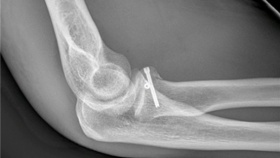

Ústecká neurochirurgie reprezentovala Evropu

- Honolulu | Neurochirurgická klinika Fakulty zdravotnických studií Univerzity J. E. Purkyně v Ústí nad Labem a Krajské zdravotní, a. s. – Masarykovy nemocnice v Ústí nad Labem, o. z., dala o sobě opět vědět na mezinárodním poli špičkové moderní medicíny.